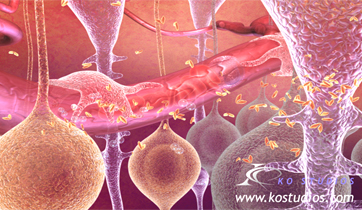

Diastolic Cardiac Insufficiency

Sanofi

ScienceProd, Paris

The Angiotensin - Aldosterone - Renin system is triggered by the thickening of the left ventricle and improper filling of the venticular chamber. This triggers the release of aldosterone, noradrenaline, and angiotensin II which binds to fibroblasts, releasing collagen and increasing myofibril rigidity.